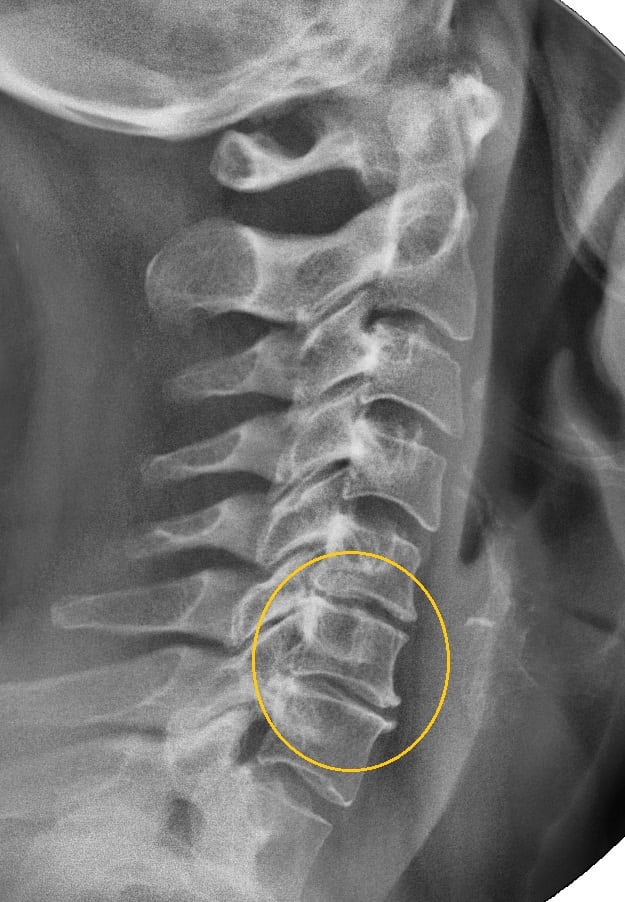

Остеохондроз шейного отдела — дегенеративно-дистрофическое заболевание, поражающее хрящевые ткани межпозвонковых дисков, провоцирующее патологическое изменение позвонков. Необходимость в госпитализации возникает только при обострении с резким ухудшением самочувствия, обычно спровоцированным пережатием позвоночной артерии сместившимся позвонком.